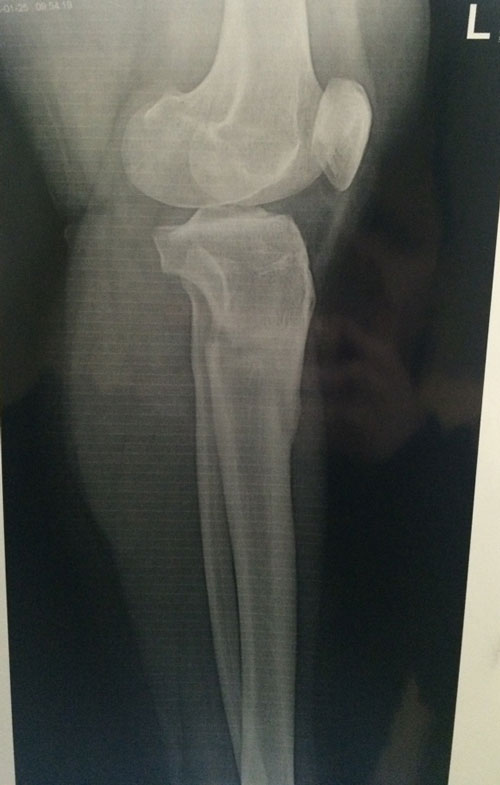

Диагноз: ахондроплазия, варусная деформация обеих голеней 155 градусов.

Исходник.